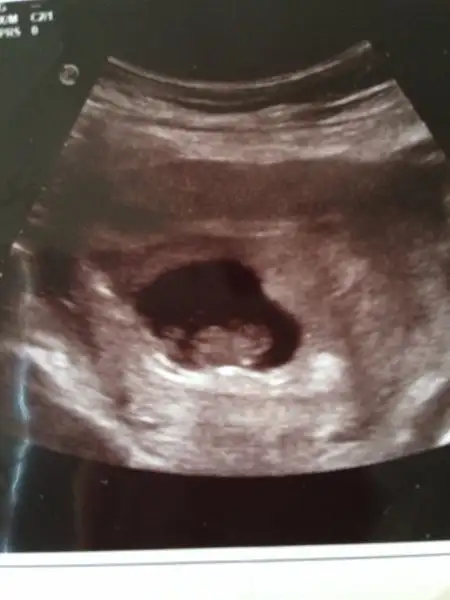

Arkasjmada oyle denislerdi iliski yasak dediker sonra kendiliginden kayboldularHanımlar yeni doktordan geldim 8 hafta 3 günlük hamileyim kesenin altında kanama alanı var dedi progestan yazdı dinlen dedi kanama alanı Zaman'la kaybolurmu bebeğimi kaybetmek istemiyorum